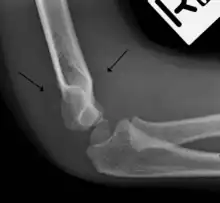

The fat pad sign is invaluable in assessing for the presence of an intra-articular fracture of the elbow. An anterior fat pad is often normal. However a posterior fat pad seen on a lateral x-ray of the elbow is always abnormal. The patient will be unable to flex their elbow and requires orthopaedic input.[2]

The posterior fat pad is normally pressed in the olecranon fossa by the triceps tendon, and hence invisible on lateral radiograph of the elbow.[3] When there is a fracture of the distal humerus, or other pathology involving the elbow joint, inflammation develops around the synovial membrane forcing the fat pad out of its normal physiologic resting place. This is visible as the "posterior fat pad sign" and is often the only visible marker of a fracture, particularly in the pediatrics population.